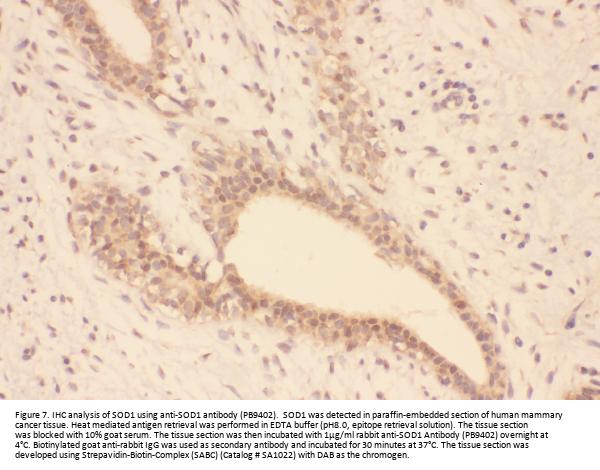

Immunohistochemistry(Paraffin-embedded Section), 2-5 μg/ml, Human

Boster Bio Anti-Superoxide Dismutase 1/SOD1 Antibody Picoband® catalog # PB9402. Tested in Flow Cytometry, IHC, WB applications. This antibody reacts with Human, Mouse, Rat. The brand Picoband indicates this is a premium antibody that guarantees superior quality, high affinity, and strong signals with minimal background in Western blot applications. Only our best-performing antibodies are designated as Picoband, ensuring unmatched performance.